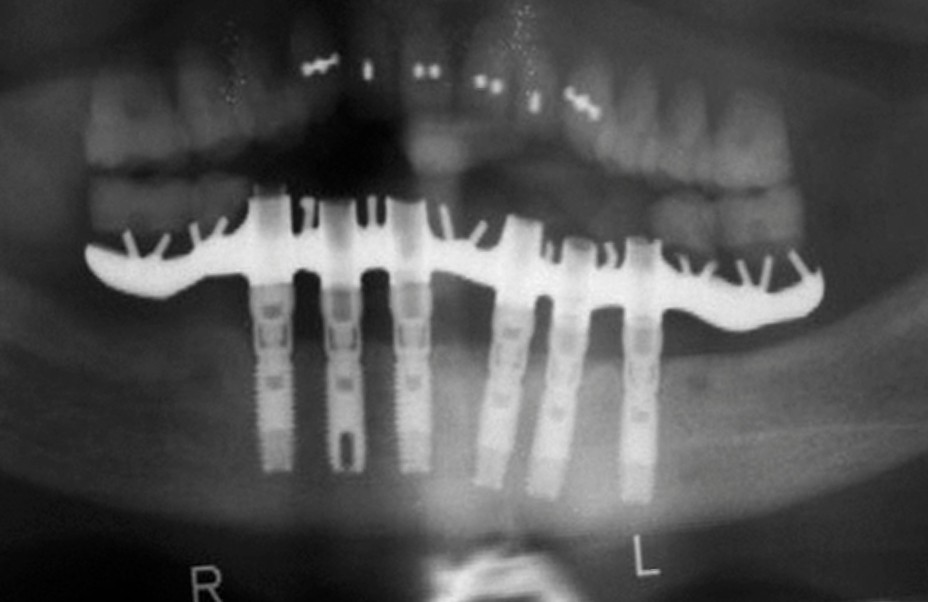

Voici quelques décennies que tout a commencé, par des réhabilitations complètes sur implants, uniquement sur l’arcade mandibulaire opposée à une prothèse amovible complète, avec le concept d’ostéointégration selon Brånemark (fig. 1) [1].

Les empreintes étaient réalisées à partir de connexions externes, les armatures étaient uniquement coulées en or ou en cobalt-chrome (fig. 2).

Le test de passivité de Jemt était obligatoire, les sections d’armatures fréquentes et la résine le seul matériau disponible. L’ostéointégration restait la seule priorité des praticiens. C’était l’implantologie chirurgicale.